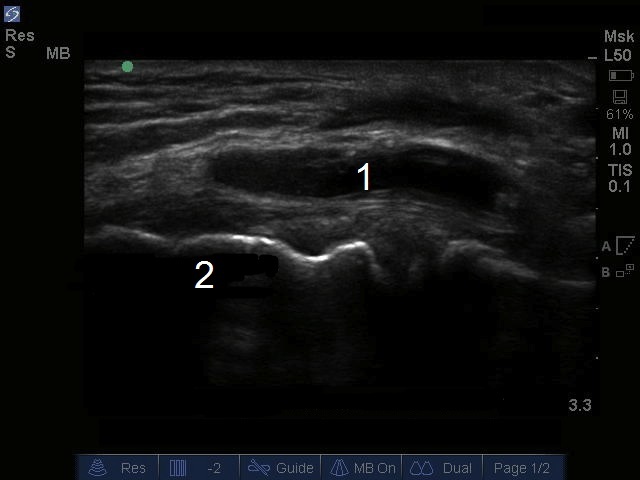

Image : Genou : Kyste du ménisque médial

Kyste du ménisque médial

Épicondyle médial du fémur